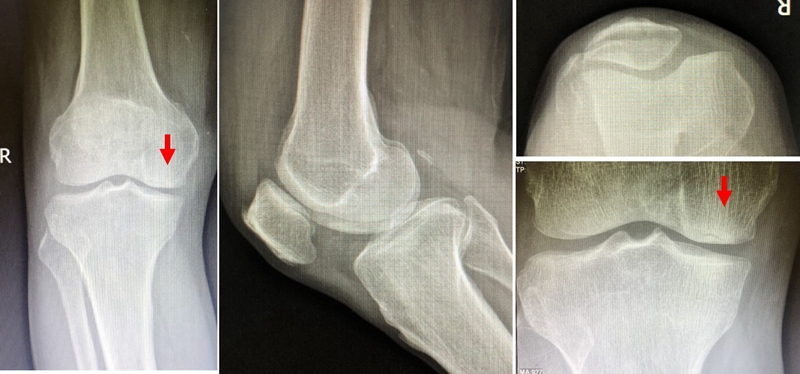

膝内翻 内侧半月板根部撕裂

关于SONK与下肢力线的关系,一项研究结果显示SONK组MPTA畸形比OA组更大,高达约1.5°,SONK组JLCA也显著高于OA组。

提示胫骨近端内翻畸形和膝关节松弛,有助于诱发SONK,SONK骨软骨病变的大小受胫骨近端内翻畸形的影响。临床中MPTA小于 84°且伴有急性膝关节疼痛应尽快MRI检查。

国内一项研究纳入内侧半月板损伤患者97例,男40例,女57例,年龄32~66岁,通过MRI测量半月板外突>3mm者38例,无半月板外突者59例。膝内翻患者半月板突出的发生率为89%,半月板根部撕裂患者半月板突出的发生率为78%,证明膝内翻、内侧半月板根部撕裂是造成内侧半月板突出的主要危险因素。